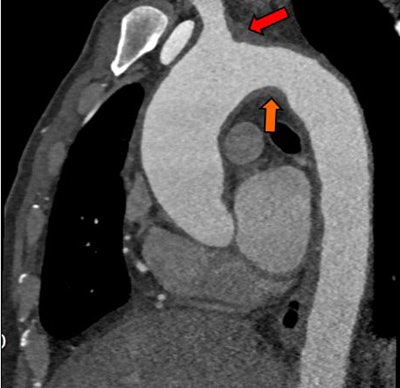

Above, an adult with a left atrial thrombus that was unreported on echocardiography and seen on CT as a filling defect on the arterial (red arrow) and delayed (orange arrow) enhancement phases. Below, an adult with remote inferior myocardial infarction that was unreported on echocardiography and seen on CT as left ventricular inferior myocardial thinning (red arrow). All images courtesy of Dr. Amr Ajlan.Scanning for cardioembolic stroke

CT found five thrombi missed by echocardiography; they were located in the left atrial body, the left atrial appendage, the left ventricular apex, a repaired mitral valve, and the aortic arch. CT did miss a thrombus at the tip of the left atrial appendage that was visualized on echocardiography and seen only retrospectively on CT.

"I think we think missed this because we did not include delayed imaging in this case," Ajlan said. "The reader probably thought it was within an adjacent cardiac recess."